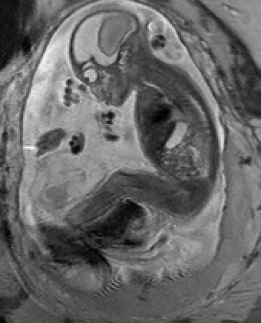

During image acquisition the fetus is not sedated and moves freely as well as the mother breathes normally. As a result, movements are likely to corrupt the scans, hiding pathology and causing overlap between different anatomical regions. In order to limit these artifacts, fast scanning sequences such as ssFSE [10] allow for the rapid acquisition of single slices at high in-plane resolution in a large field of view and good tissue contrast of the uterus. However, when acquiring a 3D volume through a stack of slices, inter-slice artifacts in the out-of-plane views are highly likely. Consequently, this restricts reliable diagnostics to individual slices in the current clinical practice. Fig. 1 depicts a typical example of motion related artifacts in a fetal single-shot fast spin echo (ssFSE) scan. The observed motion (c.f. Fig. 1 b & c) is of unpredictable nature and consists of a combination of maternal respiration movements, fetal movements and bowel movements.

Reconstruction of Fetal Organs: Exemplary PVR and SVR reconstructions under motion introduced by kicking of the fetus are shown in Fig. 11. PVR reconstruction results show an improved visual appearance and less blurring in the region with severe motion artifacts (arrow). An example of a challenging clinical case with a kidney malformation in one of twin fetuses, is shown in Fig. 8. Our clinical partners confirmed that such complications are easier to examine and to quantify after PVR-based reconstruction.